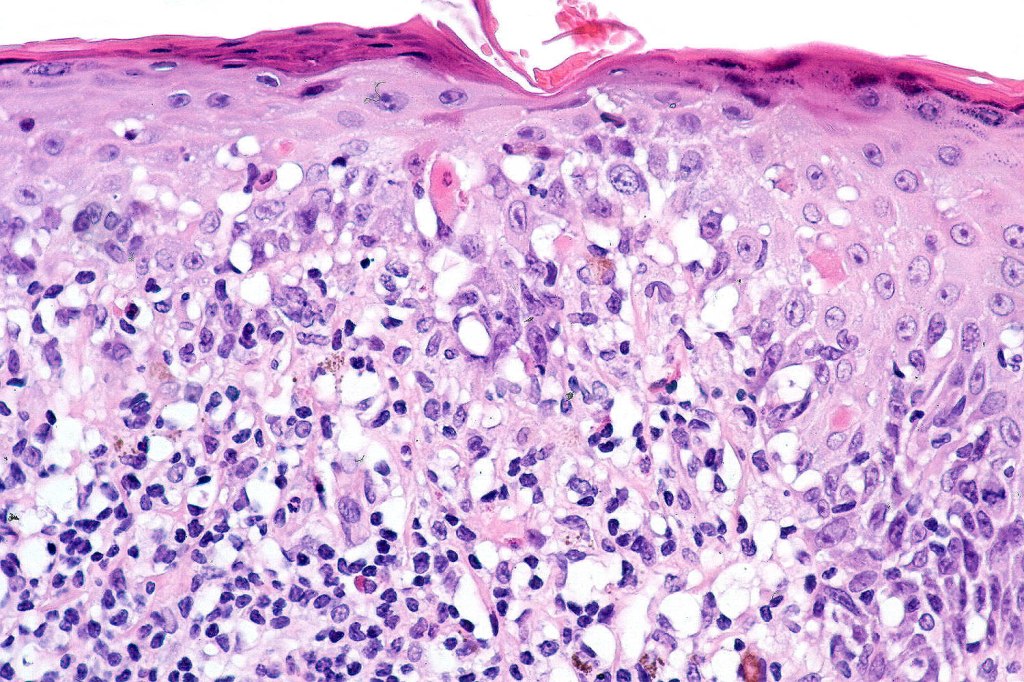

•Interface change

•Conspicuous cytoid bodies

•Pigment incontinence

•Band-like or perivascular infiltrate of lymphocytes, histiocytes with occasional eosinophils & plasma cells

•CD8+ & CD20+ lymphocytes